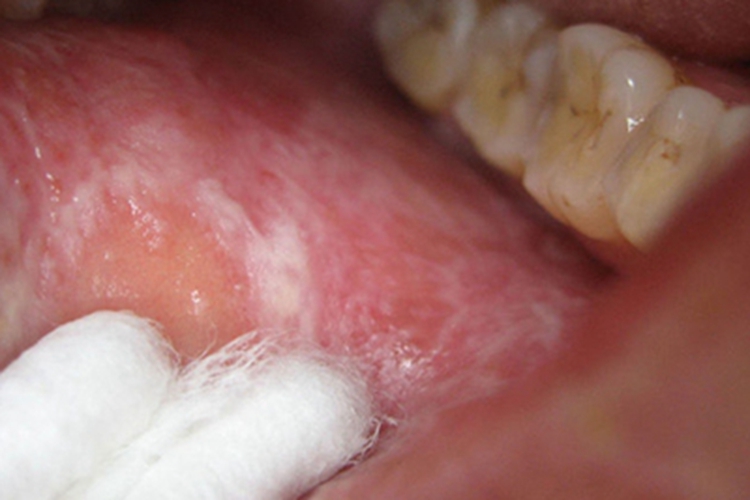

斑块型口腔扁平苔藓患者口腔黏膜可有白斑,是由针头大小的小丘疹连成白色或灰白色细条纹,之间会互相交织呈斑块状,大小、形状并不规则,黏膜发生红斑、充血。